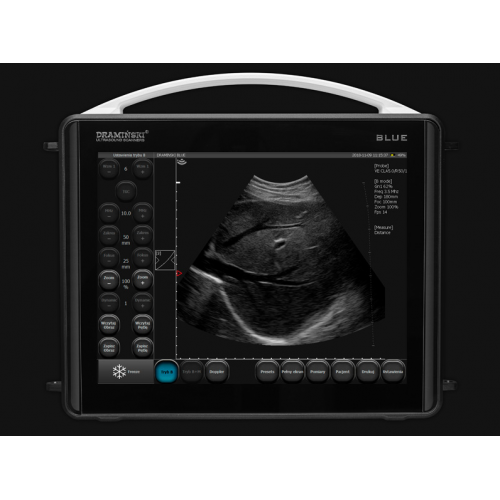

In a life-threatening situation, a correct assessment of the patient's clinical condition and speed of decision-making is important. The Blue ultrasound scanner will make both easier for you, thanks to its excellent image quality and simple and intuitive operation.

Detecting minor differences in echogenicity is possible thanks to D-Curve™, a tonal curve that is ideal for human eye perception.

LuciD ™ is a system that improves the contrast, sharpness and reproducibility of fabrics, making images clear and easy to interpret.

Vi - Probe ™ is a unique technology that allows you to get a sector image using a convex sensor and a convex image using a linear sensor. With BLUE, you'll see more, even through a small acoustic window.

The 12-inch LCD display allows you to see clear details and make the correct diagnosis. A sensitive touch panel provides function control. Thanks to this, the operation of the device is fast and simple.